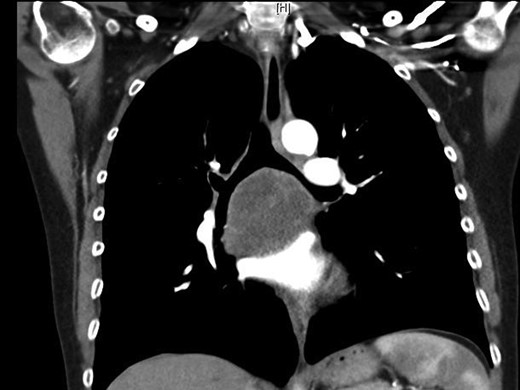

A 55-year-old Caucasian female presented with productive cough, dyspnea, chest pain and weight loss. The patient's medical history was significant for hypertension, hypercholesterolemia, dyslipidemia, chronic renal failure, gastroesophageal reflux disease and chronic anemia. She was a 30 pack-year smoker and her mother was diagnosed with lung cancer. Her physical examination was unremarkable. An initial chest X-ray showed a large subcarinal mass. On computed tomography (CT), a 6.2 × 5 cm tumor was detected in the subcarinal area (Figs 1 and 2). A bronchoscopy with transbronchial biopsy was performed, and the resulting pathological analysis was suspicious for malignant cells; however, no specific tumor type was identified. A positron emission tomography scan showed a large hypermetabolic subcarinal lesion with a standard uptake value of 14.3, consistent with malignancy. The differential diagnosis at the time included an infected bronchogenic cyst, esophageal duplication cyst or a malignant subcarinal lymph node. Thoracoscopic surgical resection was planned for diagnostic and therapeutic purposes.

Subcarinal tumor on preoperative CT of the chest, coronal cuts.